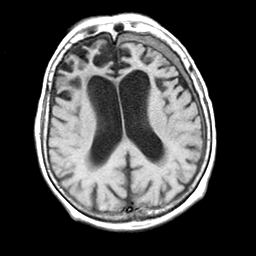

Pick's Disease, MR Study mr-t1 -- Slice #13

[Home][Help][Clinical] Slice 13